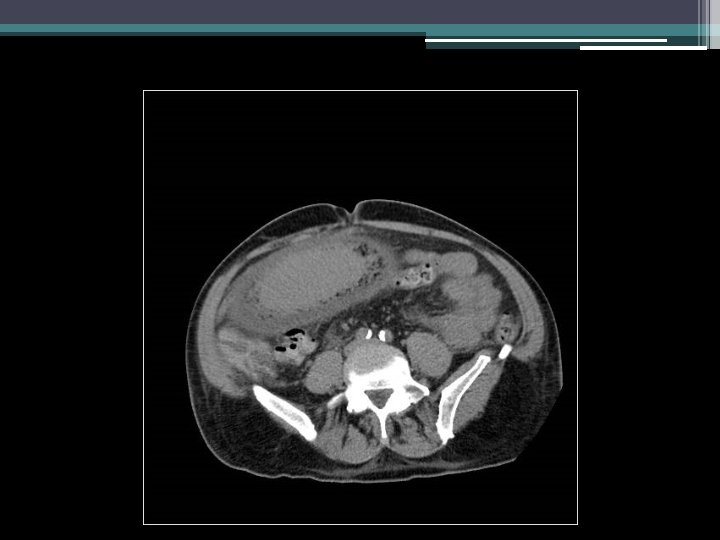

Imaging

Gastric emphysema • Diagnosis: gastric emphysema due to gastric outlet obstruction • Pneumatosis intestinalis ▫ Gastric pneumatosis Gastric emphysema Emphysematous gastritis ▫ Pneumatosis coli